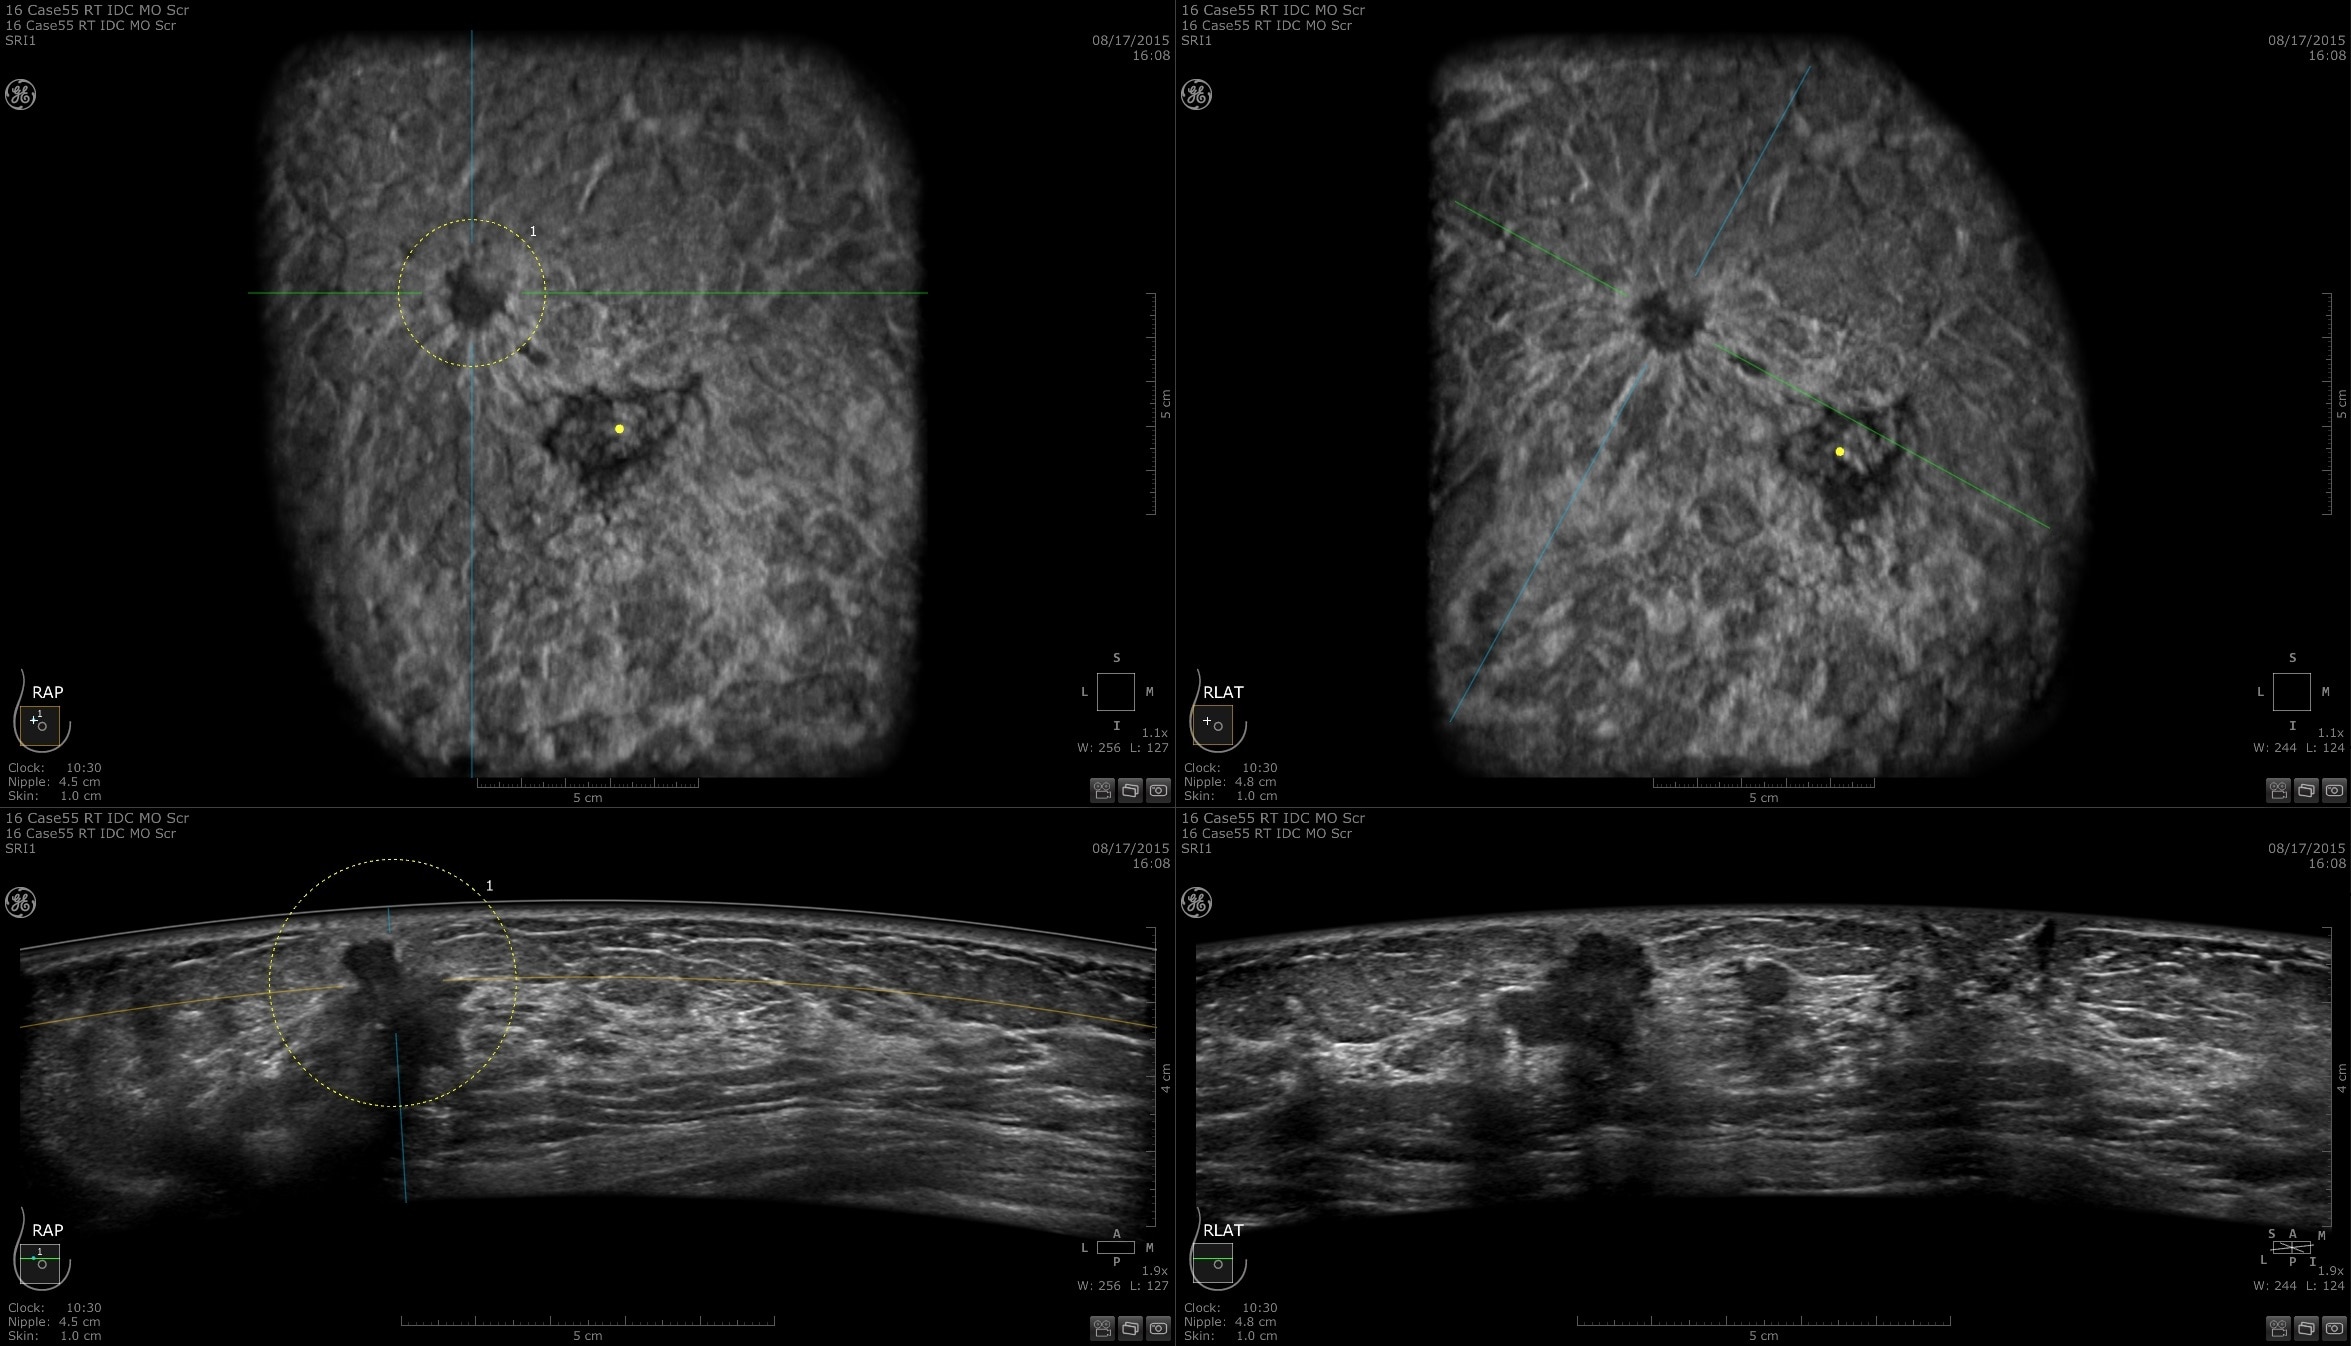

Lesion characterization for confident staging in dense breasts

Invenia ABUS 2.0 uses the latest ultrasound innovations and AI based solutions to help improve precise diagnosis and elevate clinical confidence.